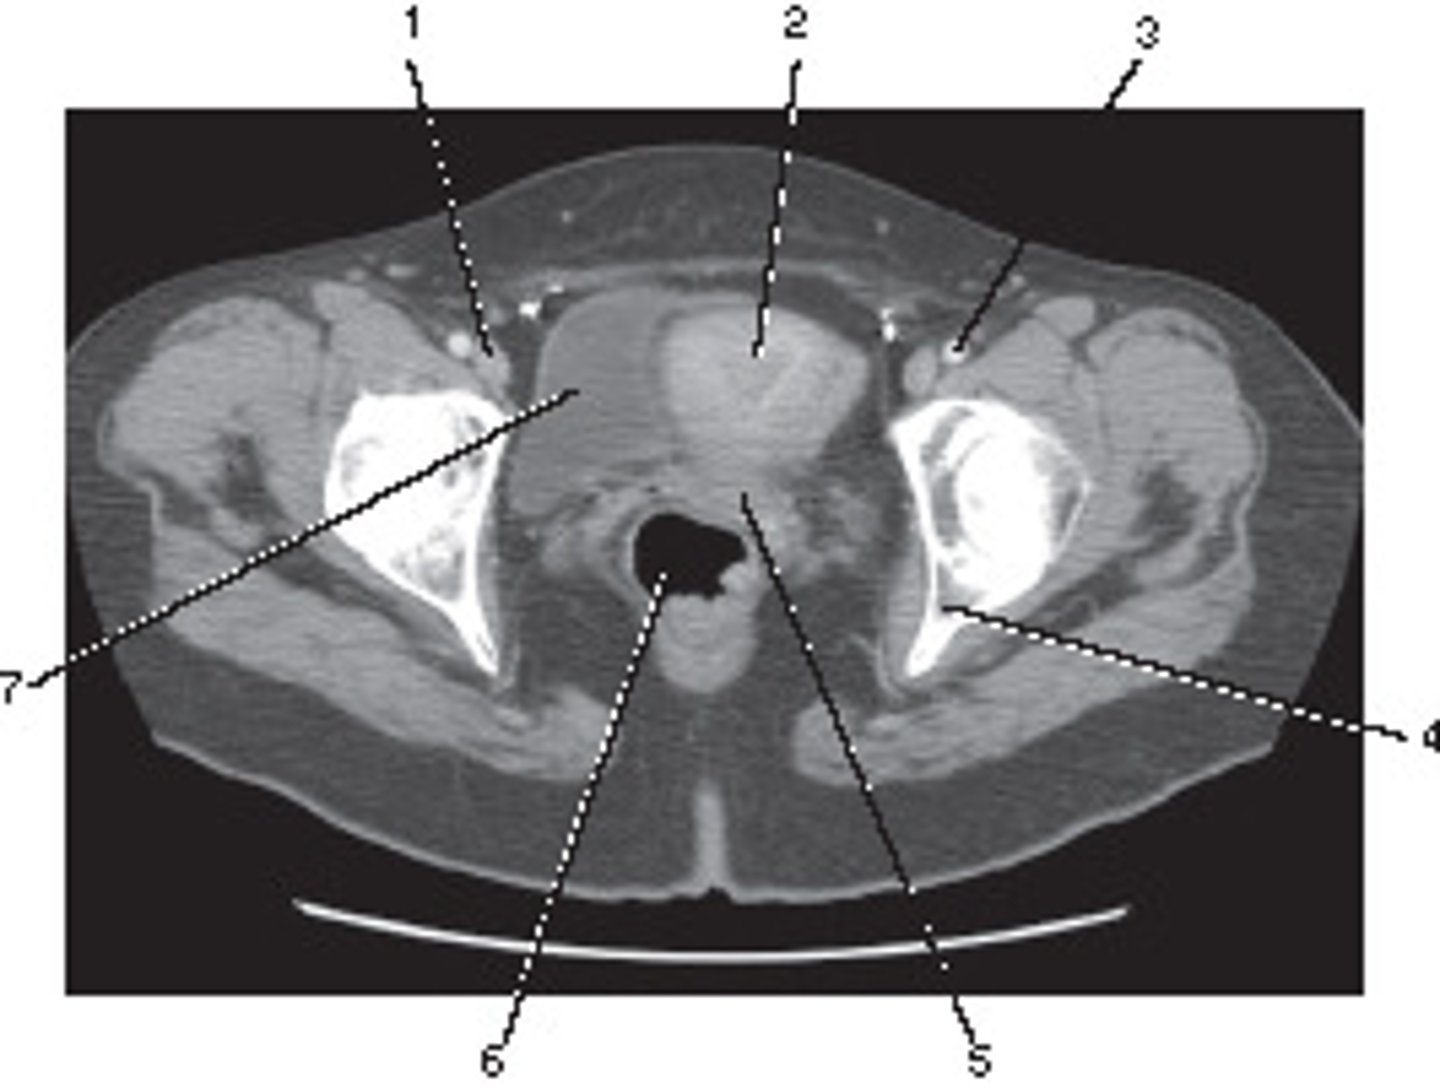

Femoral Artery

Number 1 corresponds to which of the following?

<p>Number 1 corresponds to which of the following?</p>

External Iliac Vein

Number 2 corresponds to which of the following?

<p>Number 2 corresponds to which of the following?</p>

What number corresponds to the acetabulum?

<p>What number corresponds to the acetabulum?</p>

Ilium

Number 4 corresponds to which of the following?

<p>Number 4 corresponds to which of the following?</p>